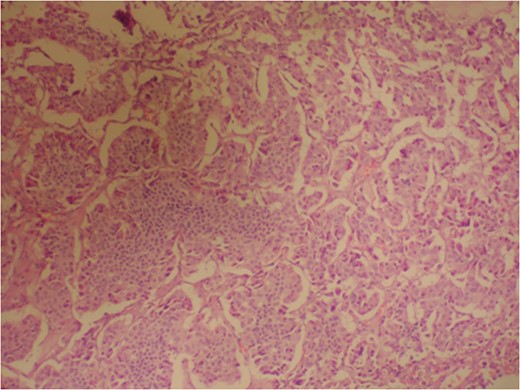

Photomicrograph indicating the tumor composed of irregular pseudopapillary structures; prominent myxoid changes can be seen in the stroma. (hematoxylin and eosin stain, ×200).

The pathologic diagnosis of SPT on light microscopy depends upon the presence of solid areas alternating with pseudopapillary formations; evidence of cellular degeneration, cholesterol clefts, nuclear grooves, aggregates of foamy histiocytes and hyaline cytoplasmic globules. Immunohistochemical staining for specific cell lineage markers is of marginal utility in proving the diagnosis of SPT. Vimentin is consistently expressed, and tumor cells are focally positive for cytokeratin and synaptophysin, and few positive for S-100 protein, CD-56 and CD-10 [7, 12].